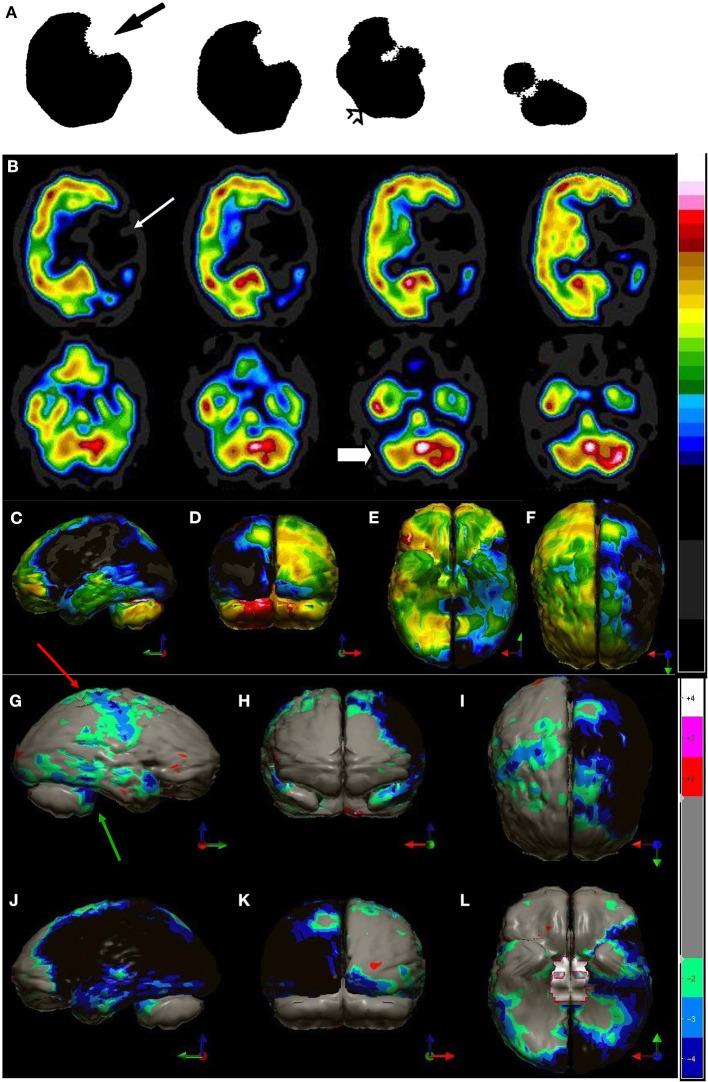

Brain perfusion single photon emission computed tomography (SPECT) scans were initially developed in 1970's. A key radiopharmaceutical, hexamethylpropyleneamine oxime (HMPAO), was originally approved in 1988, but was unstable. As a result, the quality of SPECT images varied greatly based on technique until 1993, when a method of stabilizing HMPAO was developed. In addition, most SPECT perfusion studies pre-1996 were performed on single-head gamma cameras. In 1996, the Therapeutics and Technology Assessment Subcommittee of the American Academy of Neurology (TTASAAN) issued a report regarding the use of SPECT in the evaluation of neurological disorders. Although the TTASAAN report was published in January 1996, it was approved for publication in October 1994. Consequently, the reported brain SPECT studies relied upon to derive the conclusions of the TTASAAN report largely pre-date the introduction of stabilized HMPAO. While only 12% of the studies on traumatic brain injury (TBI) in the TTASAAN report utilized stable tracers and multi-head cameras, 69 subsequent studies with more than 23,000 subjects describe the utility of perfusion SPECT scans in the evaluation of TBI. Similarly, dementia SPECT imaging has improved. Modern SPECT utilizing multi-headed gamma cameras and quantitative analysis has a sensitivity of 86% and a specificity of 89% for the diagnosis of mild to moderate Alzheimer's disease-comparable to fluorodeoxyglucose positron emission tomography. Advances also have occurred in seizure neuroimaging. Lastly, developments in SPECT imaging of neurotoxicity and neuropsychiatric disorders have been striking. At the 25-year anniversary of the publication of the TTASAAN report, it is time to re-examine the utility of perfusion SPECT brain imaging. Herein, we review studies cited by the TTASAAN report vs. current brain SPECT imaging research literature for the major indications addressed in the report, as well as for emerging indications. In Part II, we elaborate technical aspects of SPECT neuroimaging and discuss scan interpretation for the clinician.

脑灌注单光子发射计算机断层扫描(SPECT)最初是在20世纪70年代开发的。一种关键的放射性药物,六甲基丙烯胺肟(HMPAO),最初于1988年获批,但不稳定。因此,直到1993年开发出一种稳定HMPAO的方法之前,SPECT图像的质量因技术不同而有很大差异。此外,1996年以前的大多数SPECT灌注研究是在单头伽马相机上进行的。1996年,美国神经病学学会治疗与技术评估小组委员会(TTASAAN)发布了一份关于SPECT在神经系统疾病评估中应用的报告。尽管TTASAAN报告于1996年1月发表,但它于1994年10月被批准发表。因此,TTASAAN报告中用于得出结论的脑SPECT研究大多早于稳定HMPAO的引入时间。虽然TTASAAN报告中关于创伤性脑损伤(TBI)的研究只有12%使用了稳定示踪剂和多头相机,但随后有69项研究涉及超过23000名受试者,描述了灌注SPECT扫描在TBI评估中的效用。同样,痴呆症的SPECT成像也有所改进。利用多头伽马相机和定量分析的现代SPECT对轻度至中度阿尔茨海默病诊断的敏感性为86%,特异性为89%,与氟脱氧葡萄糖正电子发射断层扫描相当。癫痫神经成像也取得了进展。最后,神经毒性和神经精神疾病的SPECT成像发展显著。在TTASAAN报告发表25周年之际,是时候重新审视灌注SPECT脑成像的效用了。在此,我们回顾了TTASAAN报告引用的研究与当前脑SPECT成像研究文献,涉及该报告中讨论的主要适应症以及新出现的适应症。在第二部分中,我们详细阐述了SPECT神经成像的技术方面,并讨论了临床医生对扫描结果的解读。